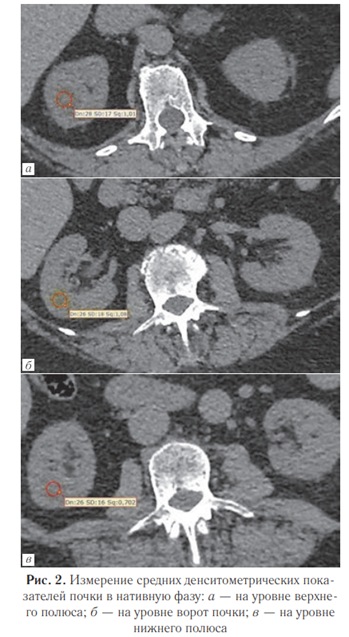

Помимо сегментации, для проведения дальнейших расчетов проводились три измерения плотности паренхимы в области полюсов почки и в области ворот каждой почки в нативной фазе (рис. 2).

Определение рационального метода расчета средних значений плотности паренхимы почек. Для определения рационального и точного метода расчета средних значений плотности паренхимы почек было проведено сравнение двух подходов:

— измерение денситометрических показателей паренхимы на трех аксиальных срезах (в области полюсов и в середине почечной паренхимы) круглым ROI и получение среднего арифметического этих измерений (рис. 4) — первый метод;

Также на основе промежуточной выборки исследований (120 пациентов) определен оптимальный метод оценки средних значений денситометрических показателей паренхимы почек. Для этого осуществлен корреляционный анализ результатов обоих изучаемых методов (первый метод — измерение круглым ROI, второй метод — измерение во фронтальном срезе) в сопоставлении с методом автоматической сегментации почек (рис. 9, а, б).

Полученное значение коэффициента корреляции для первого метода — по отдельным измерениям, составило 0,988 (p<0,001); коэффициента ковариации — 0,76 (p<0,001). Для второго метода — при обведении площади — значение коэффициента корреляции составило 0,987 (p<0,001); коэффициента ковариации — 0,73 (p<0,001). Представленные результаты свидетельствуют о высокой положительной связи.

Корреляционный анализ данных методов продемонстрировал, что обе методики допустимо использовать для измерения денситометрических значений паренхимы почек. Однако менее трудозатратная методика оценки по трем измерениям круглым ROI (первый метод) оказалась не менее точной, чем методика по одному измерению во фронтальном срезе (второй метод) при несколько лучших показателях ковариации, что позволяет остановить выбор для дальнейших расчетов на первом методе.

При сравнении двух методов оценки средней плотности (с помощью измерения круглыми ROI на аксиальных срезах и одно ROI при обведении контура на фронтальном срезе) было отмечено, что оба подхода показали высокую корреляцию (0,988 и 0,987 соответственно) с результатами автоматической сегментации. Небольшое преимущество метода трех ROI в аксиальной плоскости (ковариация 0,76 против 0,73) делает его предпочтительным, хотя оба метода приемлемы. Выбор был остановлен на методе, основанном на измерении в трех ROI, так как он более удобен в практической работе.